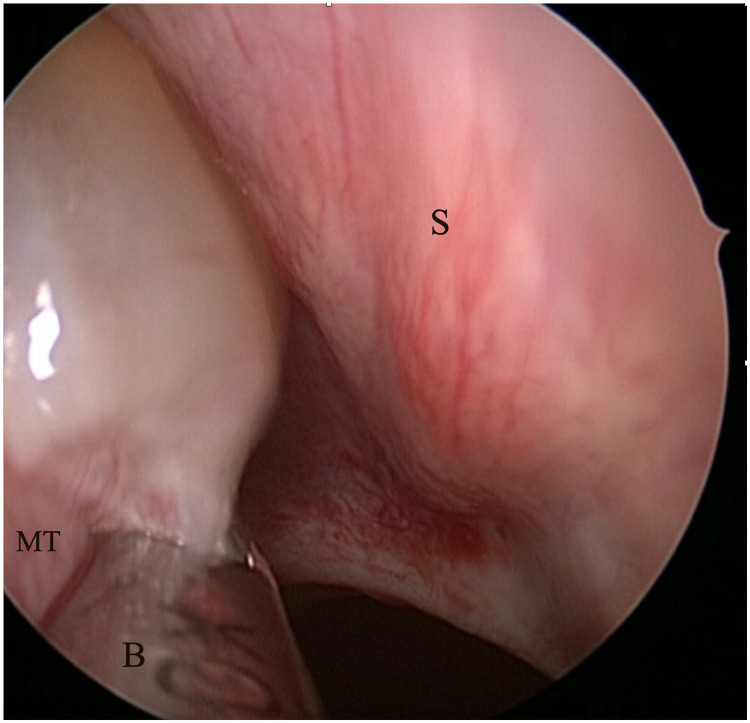

Conclusion: Our findings indicate that CCAD is significantly associated with olfactory dysfunction and that FESS can effectively improve olfactory function. To optimize postoperative olfactory outcomes, precise removal of polyps from the olfactory cleft without damaging the neuroepithelium is recommended. Our study provides valuable insights into the management of CCAD patients undergoing FESS and can guide surgical decision-making to achieve optimal olfactory function outcomes.

Abstract Image